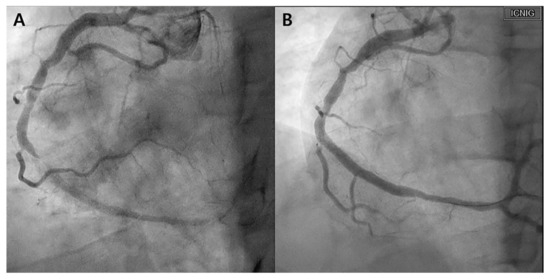

A 39-year-old man with hypercholesterolemia presented with chest pain. He had been experiencing exertional angina for 2 months, with symptoms worsening over the past 2 weeks. Atorvastatin 20 mg (Atrovan, KyungDong Pharm., Seoul, Republic of Korea) daily was prescribed for hypercholesterolemia. Upon hospitalization for suspected unstable angina, the patient underwent echocardiography and coronary angiography. Although echocardiography yielded unremarkable findings, coronary angiography revealed prominent stenosis in the distal right coronary artery (RCA), necessitating revascularization in the form of intracoronary stent implantation (Figure 1).

Figure 1. Initial coronary angiography. (A) Right coronary angiography performed before the intervention. Subtotal occlusion with flow limitation is observed in the distal right coronary artery (RCA). (B) Right coronary angiography post-intervention. After stent insertion, the RCA flow recovered.